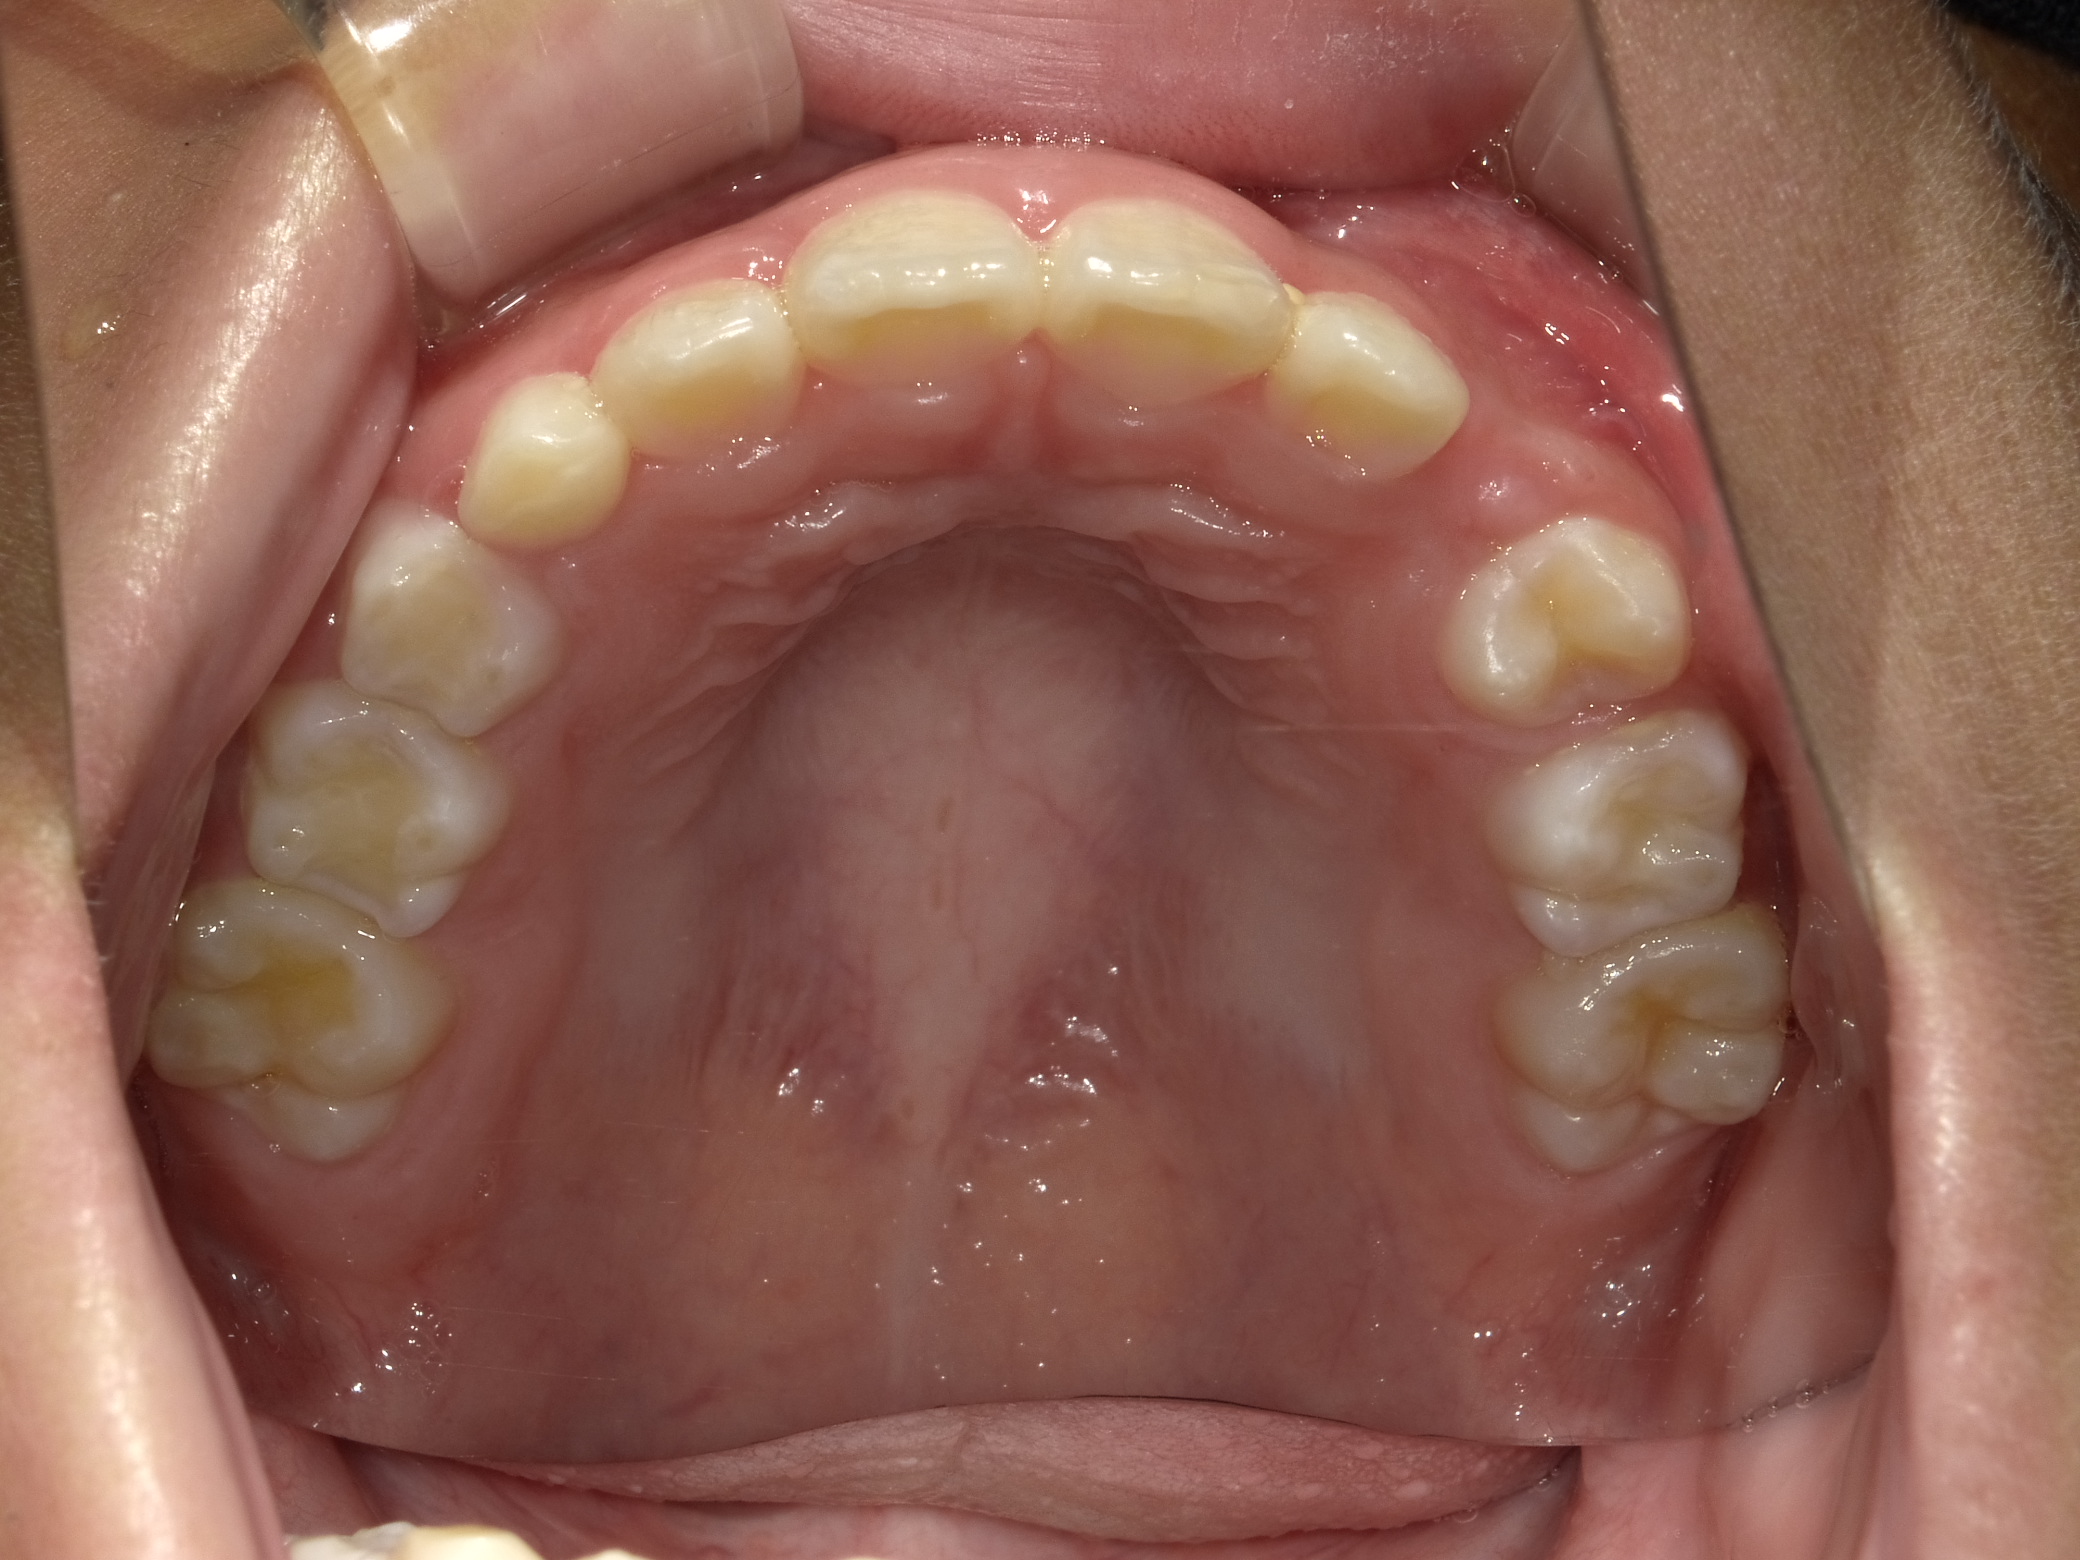

上顎

| 治療内容 | インビザライン・ファースト |

| 治療詳細 | スペース不足や交叉咬合を整えるために、歯の表面にアタッチメント(白い突起)をつけ、治療を行いました。 |

| 患者情報 | 9歳 男性 予防矯正から移行 |

| 主訴 | 永久歯は生えそろう十分なスペースがない 一部分だけかみ合わせが反対 |